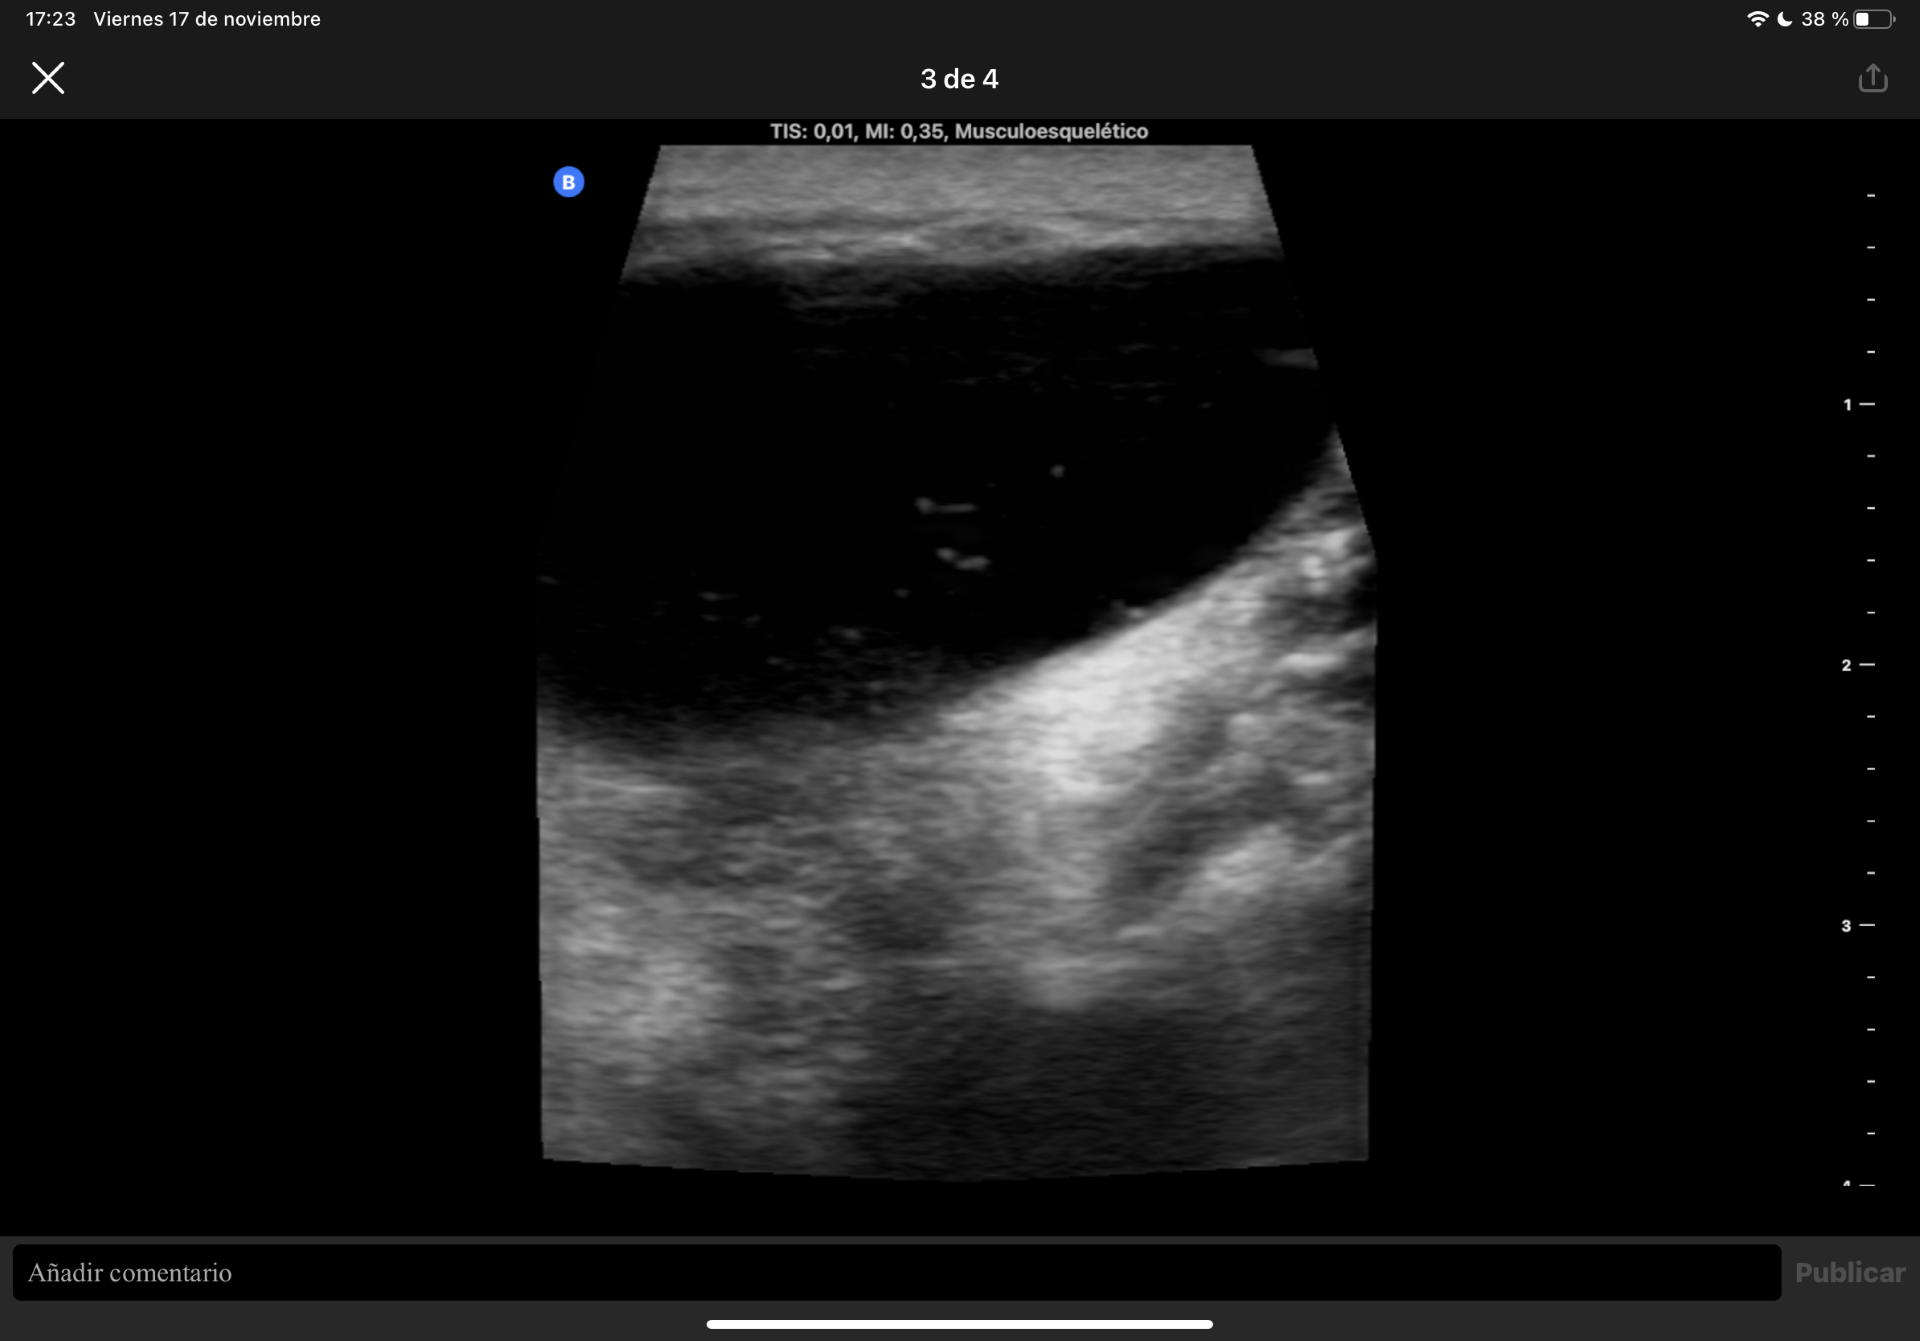

Difícil acceso por las forma de la masa. Se observa en plano dérmico lesión sin pared de 1,85 cm en su mayor altura, aneicoica con flóculos en su interior. No parece depender de la articulación del hombro ni la acromionclavicular, no se aportan más medidas por salirse de la ventana del ecógrafo.